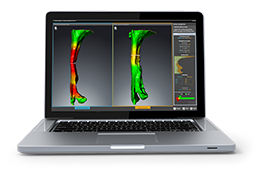

View X-Ray CT & MRI Scans Fast and Easily

FREE and easy to use 3D DICOM Viewer – for surgeons and patient education

Designed for surgeons, Pro Surgical 3D makes it easy to view patient scans quickly. Pro Surgical 3D facilitates the optimal 3D treatment and assessment workflows based on X-ray CT and MRI scans – and best of all, it’s FREE!

High-quality and fast 3D reconstruction and 3D rendering

Performs 3D reconstruction and volume rendering.